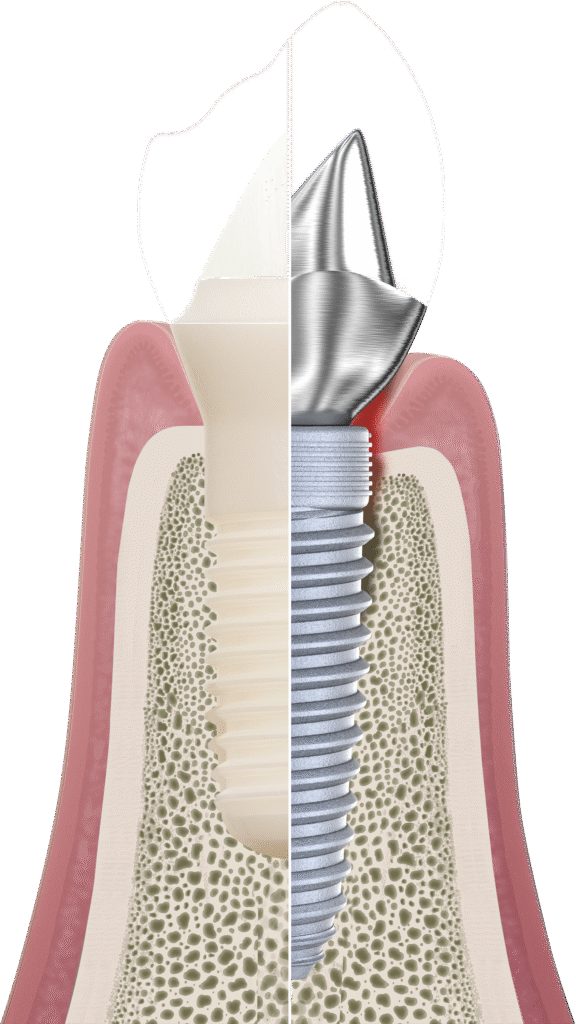

Um implante é uma raiz artificial que serve de base para um novo dente, restaurando a aparência e a função. Mas a grande questão é: que material escolher?

Os implantes de titânio são feitos a partir de ligas metálicas de titânio.

Uma resposta inflamatória similar ocorrerá no local de contato do implante dentário metálico com o osso, manifestando-se clinicamente, neste caso, por inflamação com perda do osso de suporte em torno dos mesmos (peri-implantite).

Peri-implantite: perda óssea por inflamação em torno do implante.